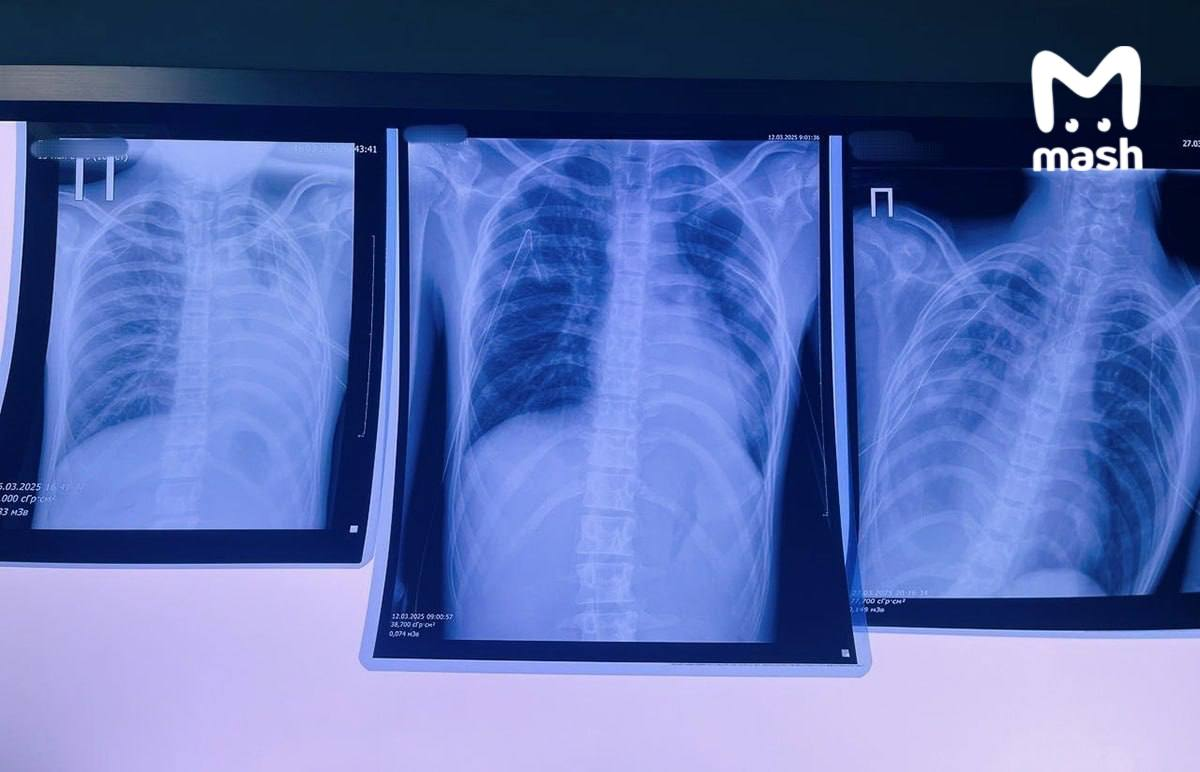

16-летние вейперы из Кировской области чуть не умерли из-за последствий курения дуделок. Школьники в больнице с сильными поражениями лёгких.

Амбассадоры вашего решения бросить бяку — девочка, которая курила сигареты 4 года и 3 — вейп (начала дымить в 12 и совмещала). Школьница жаловалась на сильный кашель с осени прошлого года, весной он усилился. Плюс начала выделяться гнойная мокрота зелёного цвета. Сейчас она в больнице с затруднённым дыханием и хрипами. У неё двусторонняя полисегментарная бронхопневмония с обструкцией бронхов.

Другой — зумер из Кирова, который вейпил несколько лет. Итог: буллы в лёгких, которые разорвались и вызвали двусторонний пневмоторакс. Его жизнь под угрозой, он в федеральной клинике под присмотром врачей.